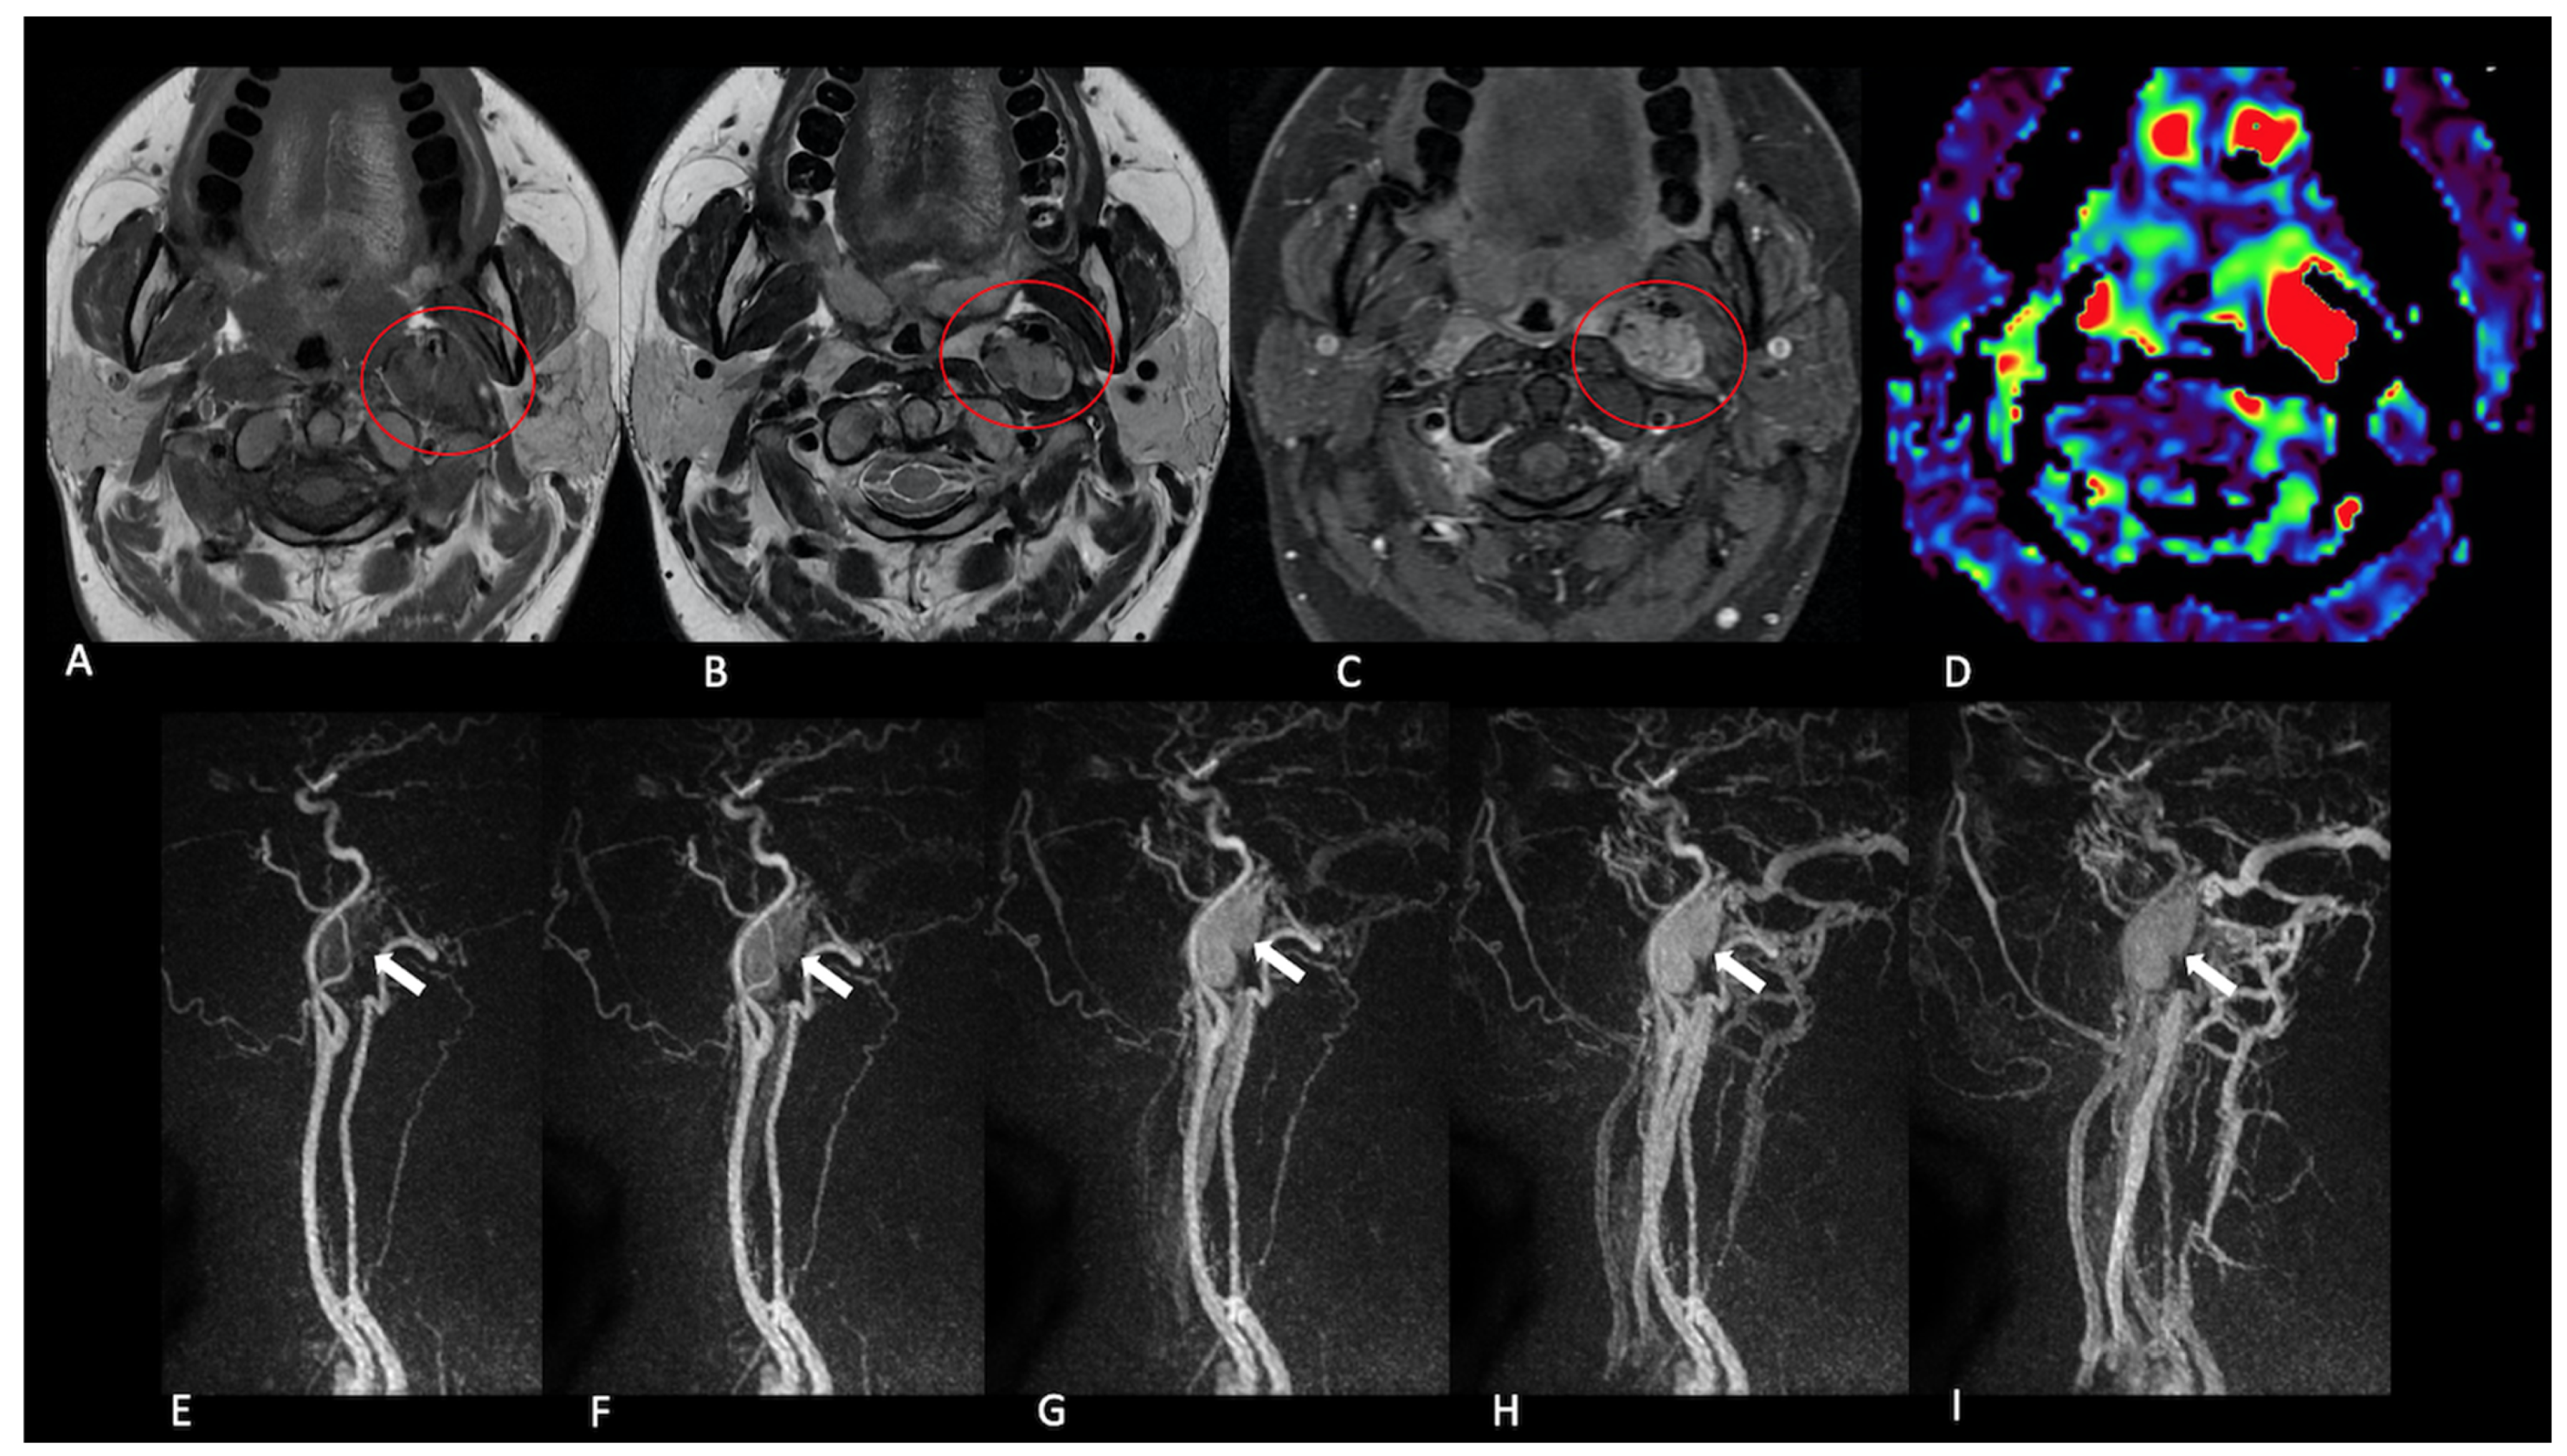

- Presence (present | indeterminate | absent) and site of a lesion.

- Sequence(s) providing greatest diagnostic confidence in detecting/localising NPGLs:

- Single sequences—FS-T2, CE-FS-T1, pcASL, and TRICKS;

- Combined sequences—FS-T2 + CE-FS-T1, and pcASL + TRICKS.